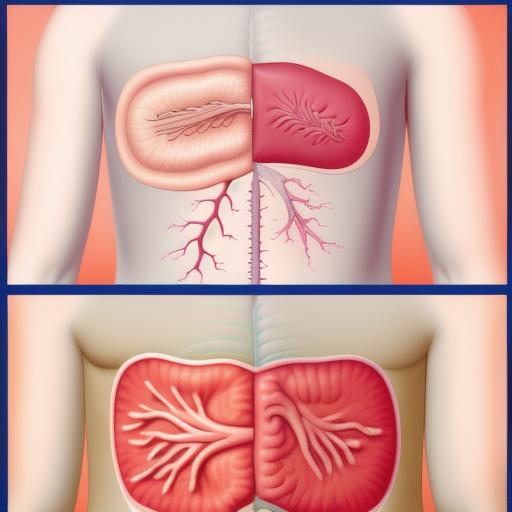

List of state leaders in the 2nd century,Cabinetry,Kidney , as a trash figure